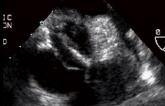

TAVR for Bicuspid Aortic Stenosis? Registry Offers Clues to Safety, Outcomes

News Conference News ACC 2017

Post-TAVR, Nearly a Quarter of Patients Show New Signs of Silent Cerebral Microbleeds on MRI

SURTAVI Lends More Support to Use of TAVR in Intermediate-Risk Patients